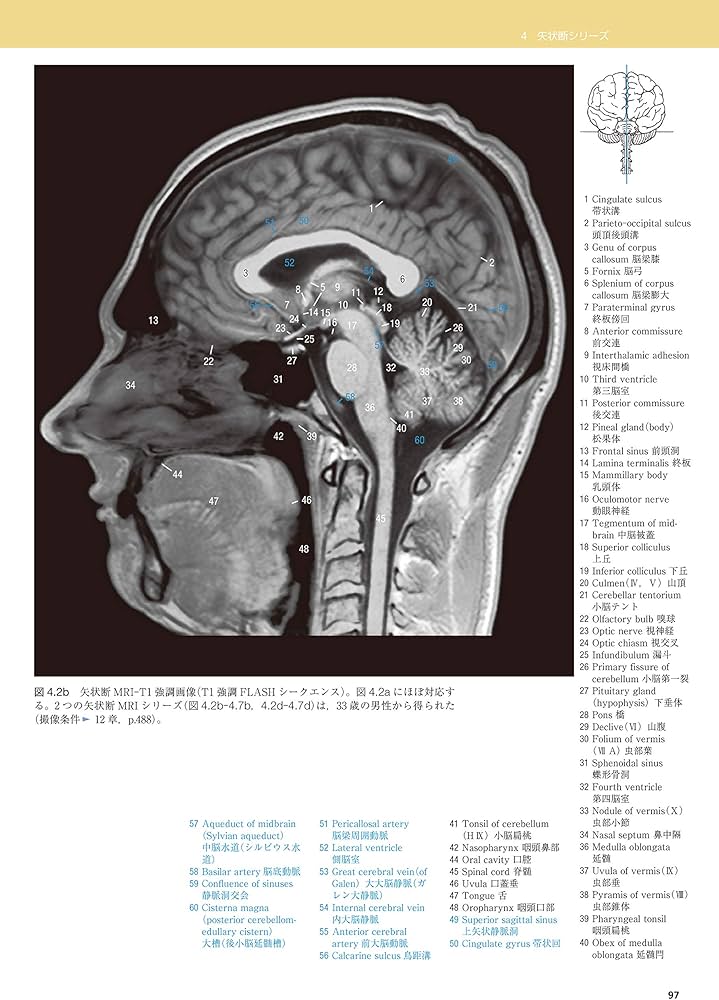

ほとんど未使用です。書き込みなし。※裁断はしていません。「脳の機能解剖と画像診断」 第2版眞柳 佳昭定価: ¥ 20000#眞柳佳昭 #眞柳_佳昭 #本 #自然/医療・薬学・健康